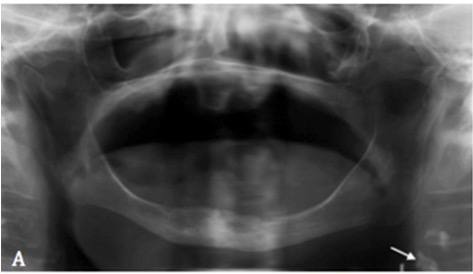

2. What condition can be seen in the following X ray? ( Open arrow)